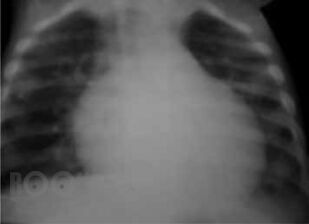

В пособии освещены современные концепции этиопатогенеза наиболее распространенных хирургических заболеваний детского возраста – гнойно-воспалительных заболеваний мягких тканей; различных форм гематогенного остеомиелита; деструктивных пневмоний; бронхоэктатической болезни; гнойно-воспалительных заболеваний мочевыделительной системы и органов брюшной полости – их диагностика и дифференциальная диагностика, современные методы консервативной терапии и оперативного лечения; критерии диагностики сепсиса и принципы рациональной антибиотикотерапии у детей. Пособие предназначено для студентов, обучающихся по специальности «Педиатрия», «Лечебное дело», «Медико-профилактическое дело».